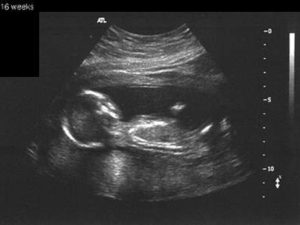

УЗИ на 17 неделе беременности уже может показать пол ребенка, если он повернется к датчику тем самым местом. Однако врача будут волновать другие показатели: размеры малыша и матки и их соответствие сроку, сердцебиение плода, его двигательная активность, состояние маточного миометрия, околоплодных вод, отсутствие грубых аномальных нарушений и так далее.

УЗИ показывает наличие сердцебиения у малыша. На экране монитора вино плодное пустое яйцо, или уменьшенные размеры эмбриона.

- Второе плановое УЗИ (показывает развитие ребенка в утробе матери) или повторный скрининг;

По данным УЗИ размеры эмбриона меньше положенного срока беременности. Сердцебиение у него отсутствует.

При УЗИ также можно выявить анэмбрионию — разновидность неразвивающей беременности, когда плодное яйцо пустое, без эмбриона.

При проведении УЗИ на 17 неделе беременности проводится:

- фетометрия (определение размеров плода);

- диагностика развития внутренних органов;

- оценка развития структуры лица;

- количество околоплодных вод;

- кроме того, специалист проверит, в каком состоянии находится плацента.